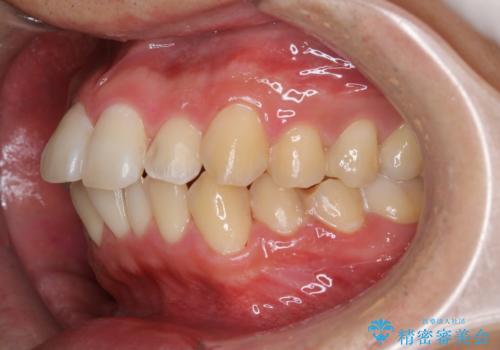

セラミックを付ける前にエアフローで綺麗ににクリーニング

- セラミックの詰め物を付ける前に、全体のクリーニングを希望とのことでした。

染め出しをし、歯磨き指導とクリーニング(エアフロー60分コース)を行いました。